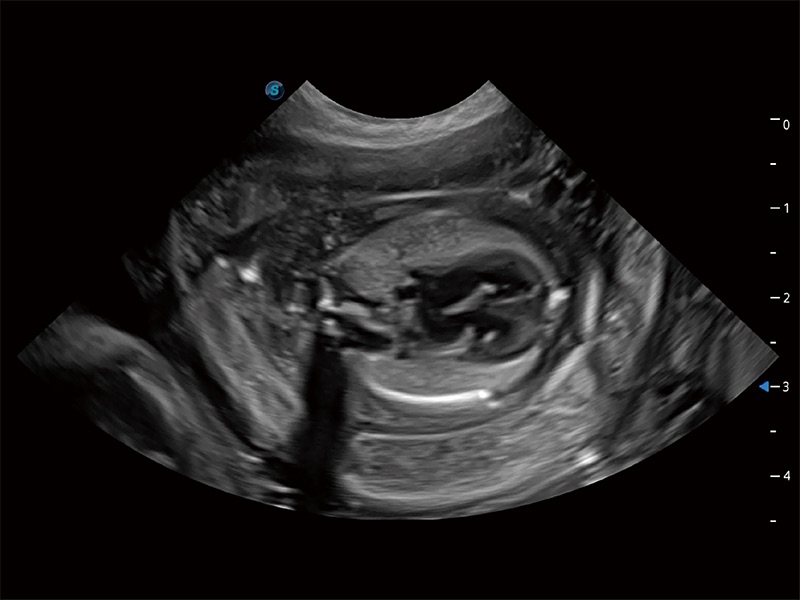

高性能和先进的临床应用工具可以为动物医生提供临床信心。ProPet 80 搭载了先进的腹部和浅表应用工具,帮助医生在日常临床实践中发挥前所未有的作用。

操作简便,无需高频度外力作用即可真实反映组织的形变,快速评估肿瘤良恶性。

非线性融合造影成像充分利用谐波和基波信号,为难以观察的血流进行增强显像。可用于线阵、凸阵、微凸阵、相控阵探头。